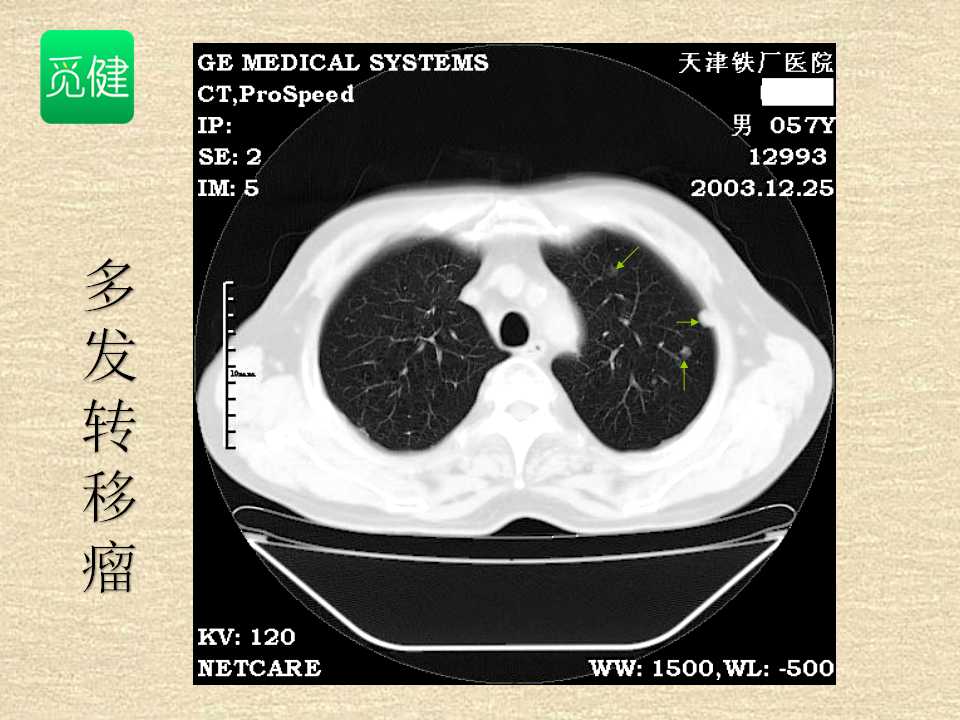

肺癌影像学表现